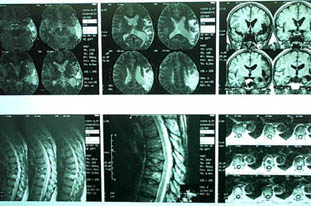

Уважаемые участники форума, Больной 53 лет, с жалобами на выраженные боли в области грудного отдела позвоночника, чувство онемения и стягивания в правой кисти, боли в мышцах конечностей и туловища. Отмечается парез правой верхней конечности.

В декабре 99 года перенес геморрагический а потом и ишемический инсульт левой задне-лобно-височной области. Выписался со значителсным улучшением неврологической симптоматики. Через год, на фоне обычного самочувствия, пожаловался на боль в спине, после чего появилось тоническое напряжение правой руки, половины туловища, перерастающее в приступ с судорогами по типутонико-клонических и потерей сознания. Госпитализирован. На CТ выявлен большой очаг в виде кистозной полости. Компрессионный перелом 8-9 грудных позвонков. В последующем, на протяжении полутора лет в общей сложности отмечено 5 аналогичных по формуле припадков. Падения с высоты во время приступов небыло. Также отрицает травмы позвоночника в анамнезе. ПовторнаяR-графия и СТ позвоночника выявила патологический компрессионный перелом и остеопороз тел Th 6; 7; 8; 9, (отрицательная динамика). Наличиенеобластомного процесса не выявлено. Все анализы, включая паратгормон, впределах нормы кроме:Са-Т - 2.66 (от 2.02 до 2.60)Р - 1.72 (от 081 до 1.62)СОЭ - 34мм/часСнимки 1, 2, 3, 4 прилагаются.Возникает ряд вопросиов: Может ли деструкция в левой задне-лобно-височной области быть связана с системним остеопорозм позвонков и пат. переломом? Моигут ли эпилптические приступы явиться причиной компрессионного переломапозвонков? Какие дополнительные исследования нужны для дифдиагностики болезни Куммелля? Тактика лечения (корсет?), показания и противопоказания к хирургическому вмешательству на позвонках в данной ситуации Прогноз?Буду благодарен любым соображениям,Аршак Мирзоян

imaging (MRI) may be able to do so. Materials and Methods: Patients

who underwent MRI evaluation for vertebral collapse were

retrospectively studied. Over a 21-month period from January 1995 to

September 1996, 47 patients with 58 vertebral collapses were studied.

Benign and malignant aetiologies were established by serial imaging,

clinical outcome and histology. Imaging was performed with T1 and

T2-weighted sequences, with contrast enhancement in some patients.

Collapsed vertebrae were examined for appearance of marrow on T1

and T2-weighted sequences and after contrast administration, signal

intensity of adjacent discs, degree of marrow involvement, involvement

of posterior elements, presence or absence of paraspinal mass and

end-plate integrity. Agreement between the final and radiological

diagnosis was evaluated. Results: There were 36 benign vertebral

collapses (20 osteoporotic, 7 post-traumatic, 9 infective) and 22

malignant ones (20 metastatic carcinoma, 2 multiple myeloma). Features

which pointed t o malignant cause were hypointense marrow on

T1-weighted images, marrow enhancement after intravenous contrast,

greater than 50% marrow involvement and involvement of posterior

elements. Of the vertebral collapses due to infection, 78% showed

end-plate disruption. Conclusions: This study shows that MRI can be

used to accurately differentiate between benign and malignant causes

of vertebral collapse. Further differentiation between an

osteoporotic, traumatic or infective cause can be done with the help

of clinical history and evaluation of end-plate integrity.

Ann Acad Med Singapore 2002; 31:8-14